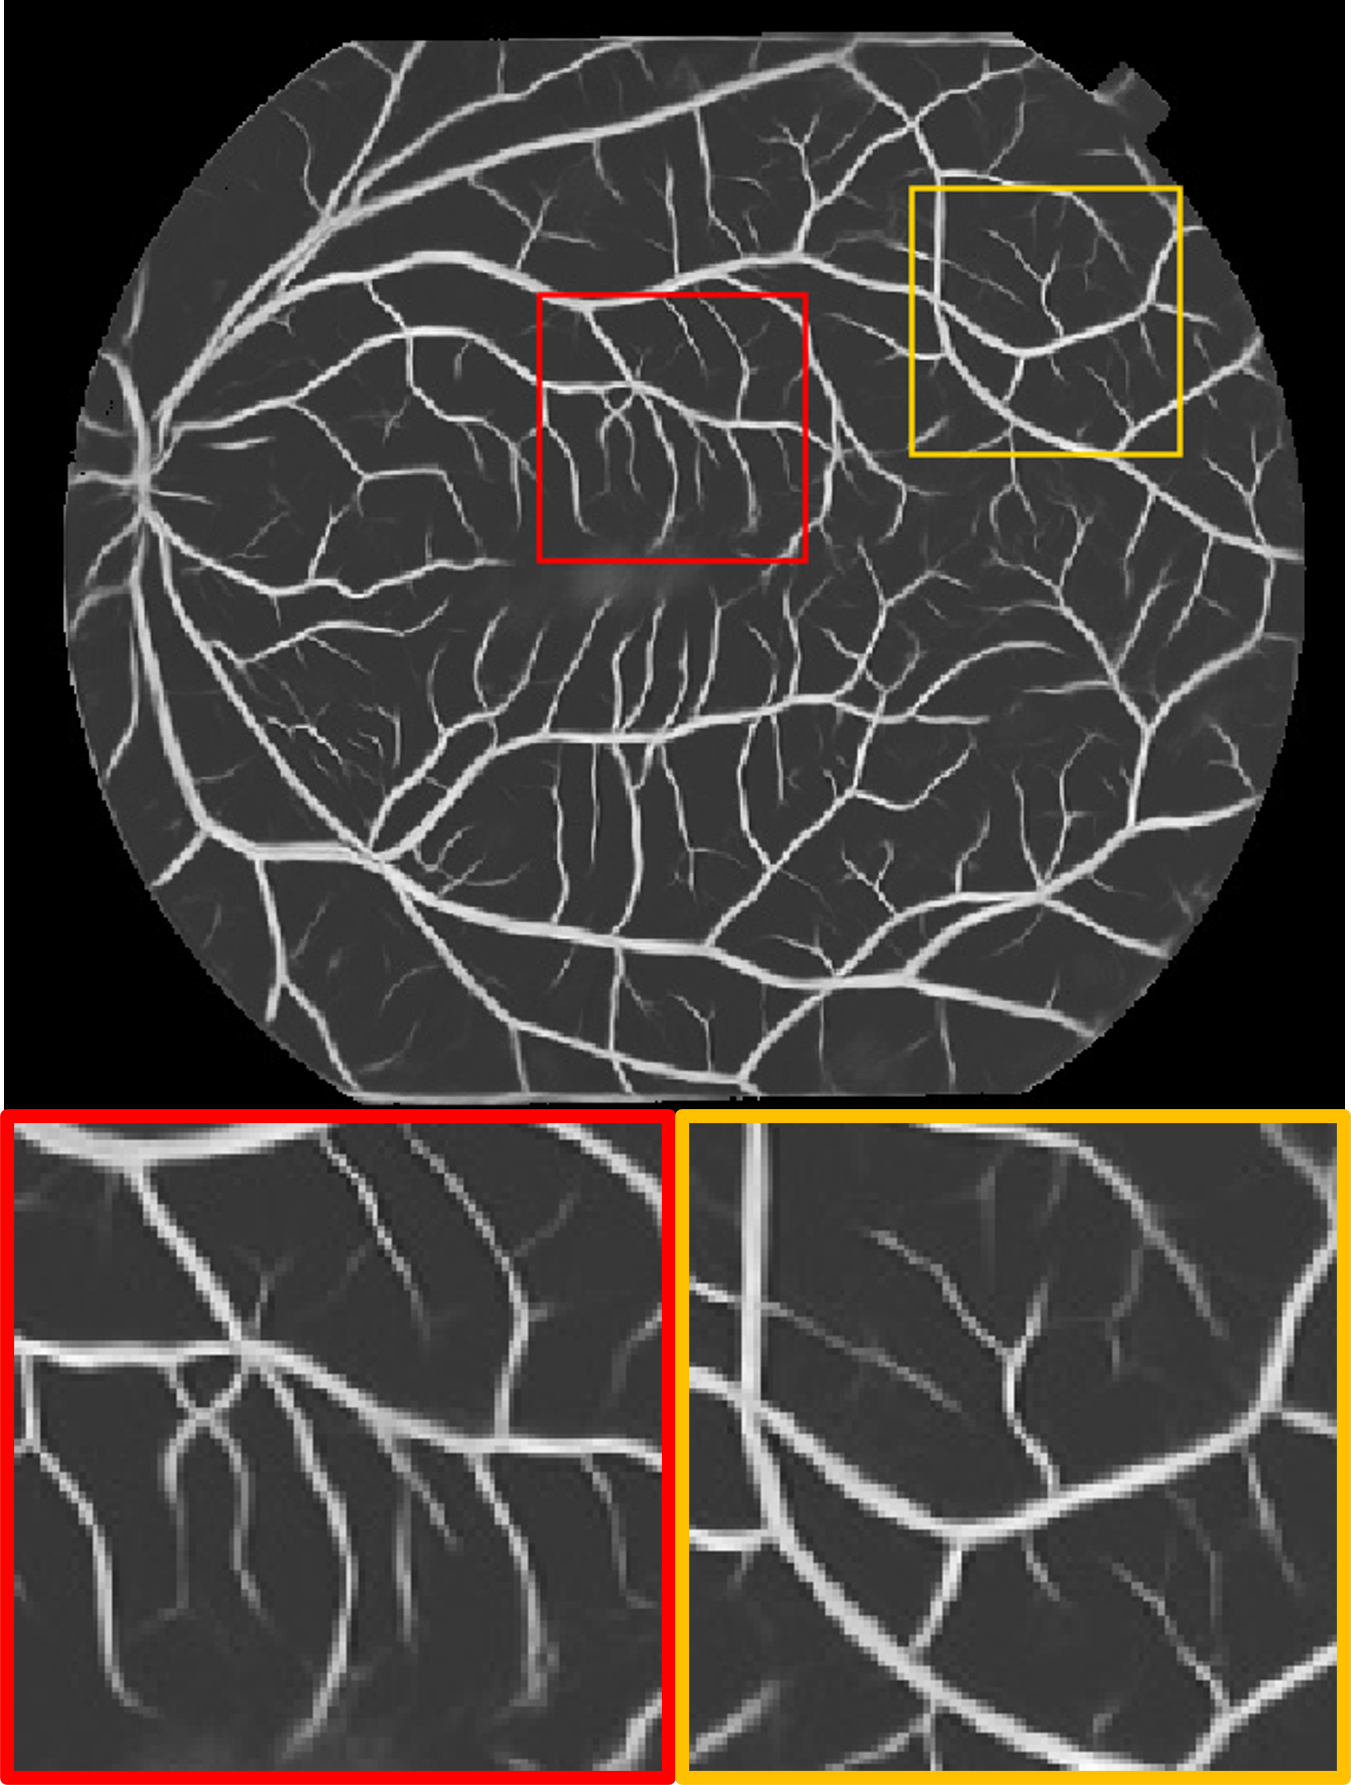

Datasets. We use four publicly available fundus datasets as shown in Fig. 1(b). The DRIVE dataset [15] consists of 20 labelled images of size . The HRF dataset [16] contains 45 labelled images of size . The STARE dataset [17] includes 20 labelled images of size . The ARIA dataset [18] includes 138 labelled images of size . DRIVE and HRF are set as source domain, whereas STARE and ARIA are used for testing.

Fig. 2 shows a test example from each of the target domains. We observe that for different datasets, the manual annotations includes varying amounts of detail: the label for the STARE dataset contains many more small vessels than ARIA. In the ARIA example, the deep angiogram is able to enhance the thin vessels with very poor contrast. This is also evident by the big vessels seen at the bottom left quadrant of the image where the illumination is low. Moreover, the angiogram filters out the circular artifacts seen within the red box. In the STARE example, our model extracts most of the vasculature including the faintly visible fine vessels. These tiny vessels have relatively lower intensity in the deep angiogram, which suggests lower confidence. Compared to the manual label, the deep angiogram can also delineate the vessel diameter more precisely.